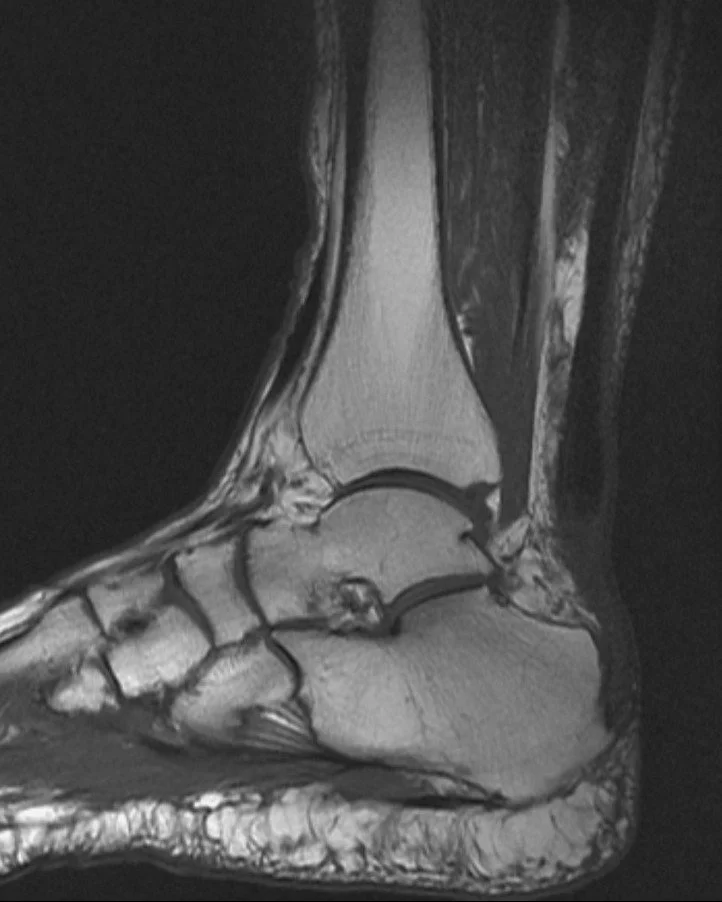

When an injury occurs in an area where there is very little blood flow (ligament, tendon or joint), it makes for difficult healing. Occasionally rest, traditional osteopathy, physical therapy, and other modalities do not quite lead to complete repair, leaving you with pain and decreased function. An ultrasound guided PRP injection may be just the support your body needs to supply the healing factors that will help decrease your pain and return you to full function.

Injuries to tendons (the fiberous portion of muscle that attaches to bone) and Lilgaments (Fiberous bone to bone attachments across joints) are common with sports, physical labor, and in older age. Occasionally these injuries do not heal quickly despite proper rest, physical therapy and traditional osteopathy. Some will require surgery, others may benefit greatly from a PRP injection.